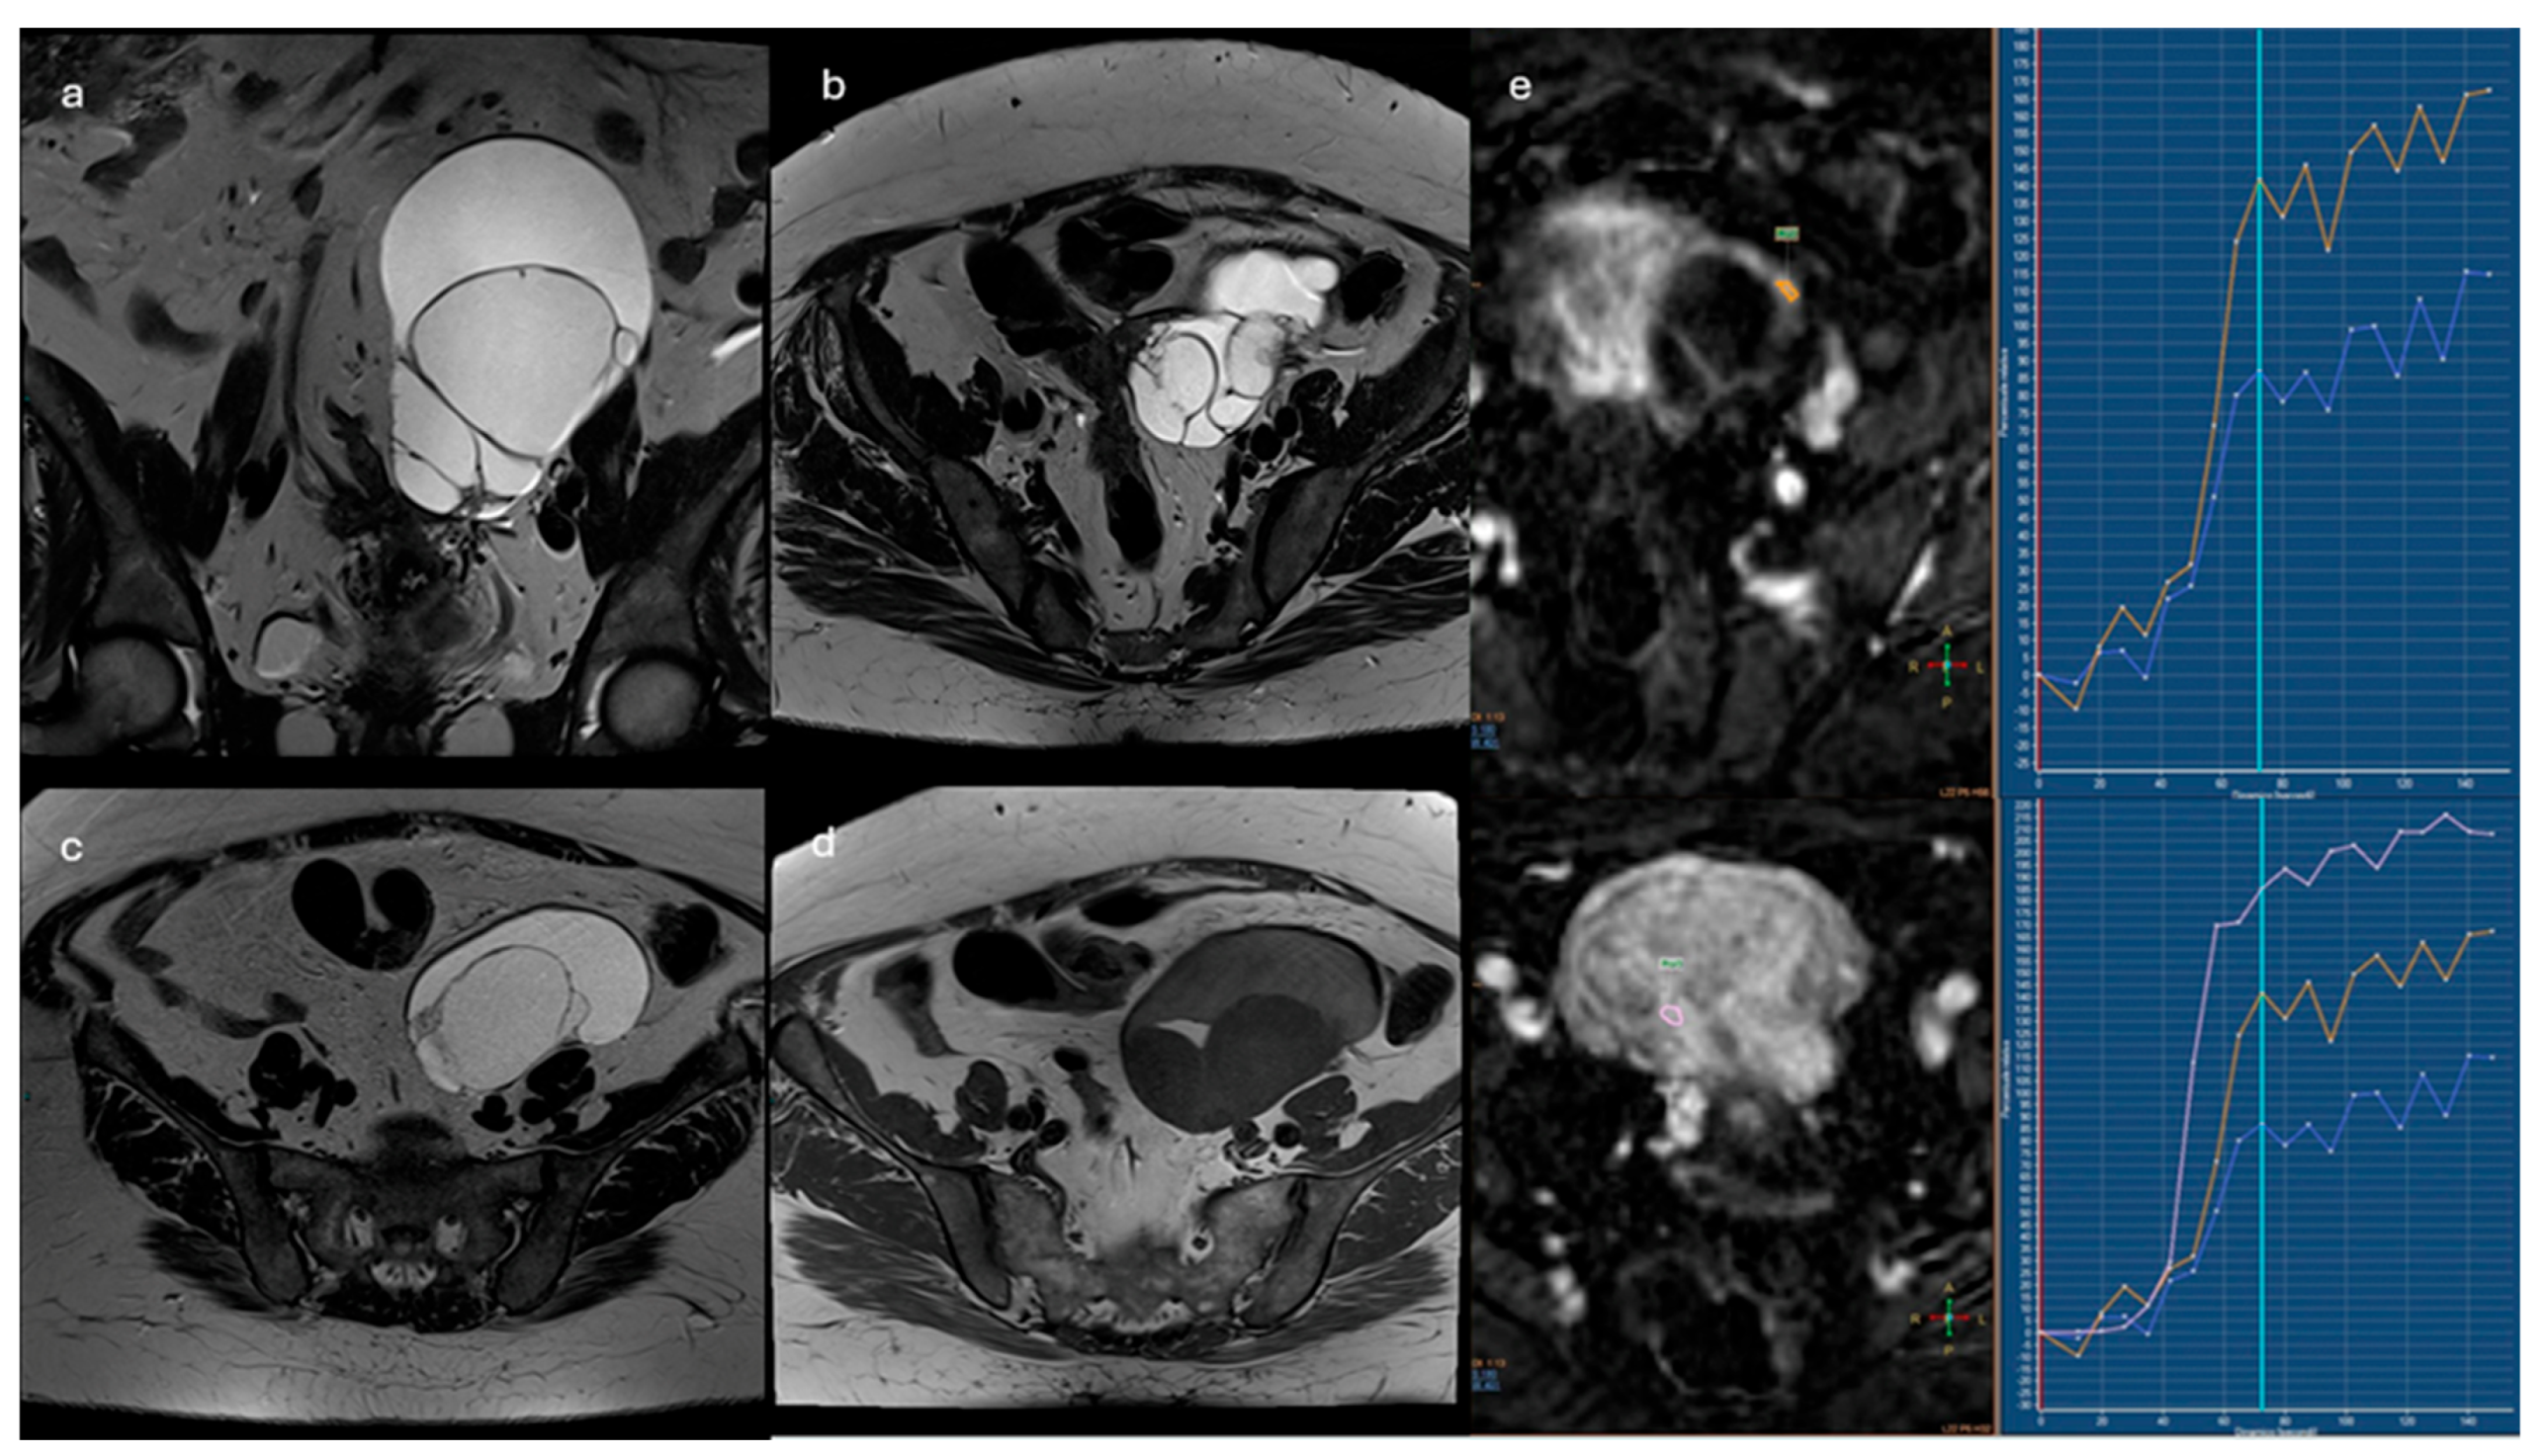

2.3.1. ADNEX-MR Scoring System

- Absence of ovarian lesions

- Benign lesions: lesions with homogeneous content (serous, blood, fat) and the absence of wall enhancement and/or with hypointense solid tissue signal in T2 sequences and at high b values

- Probably benign lesions: absence of solid tissue or solid tissue with type 1 enhancement curve

- Indeterminate lesions: presence of solid tissue with type 2 curve

- Likely malignant lesions: type 3 enhancement curve and presence of peritoneal implants

2.3.2. O-RADS MRI Score

- Type1(low risk): slower increase in signal intensity (enhancement) of solid tissue than that of the myometrium, without a peak or plateau

- Type 2 (intermediate risk): moderate initial increase in solid tissue signal with a slower or equal slope to that of the myometrial, followed by a plateau

- Type 3 (high risk): pronounced signal increase with an early peak compared with that of myometrium

- Lesions with solid tissue (excluding solid lesions described in score 2) showing type 2 enhancement curve (intermediate risk; Figure 4)